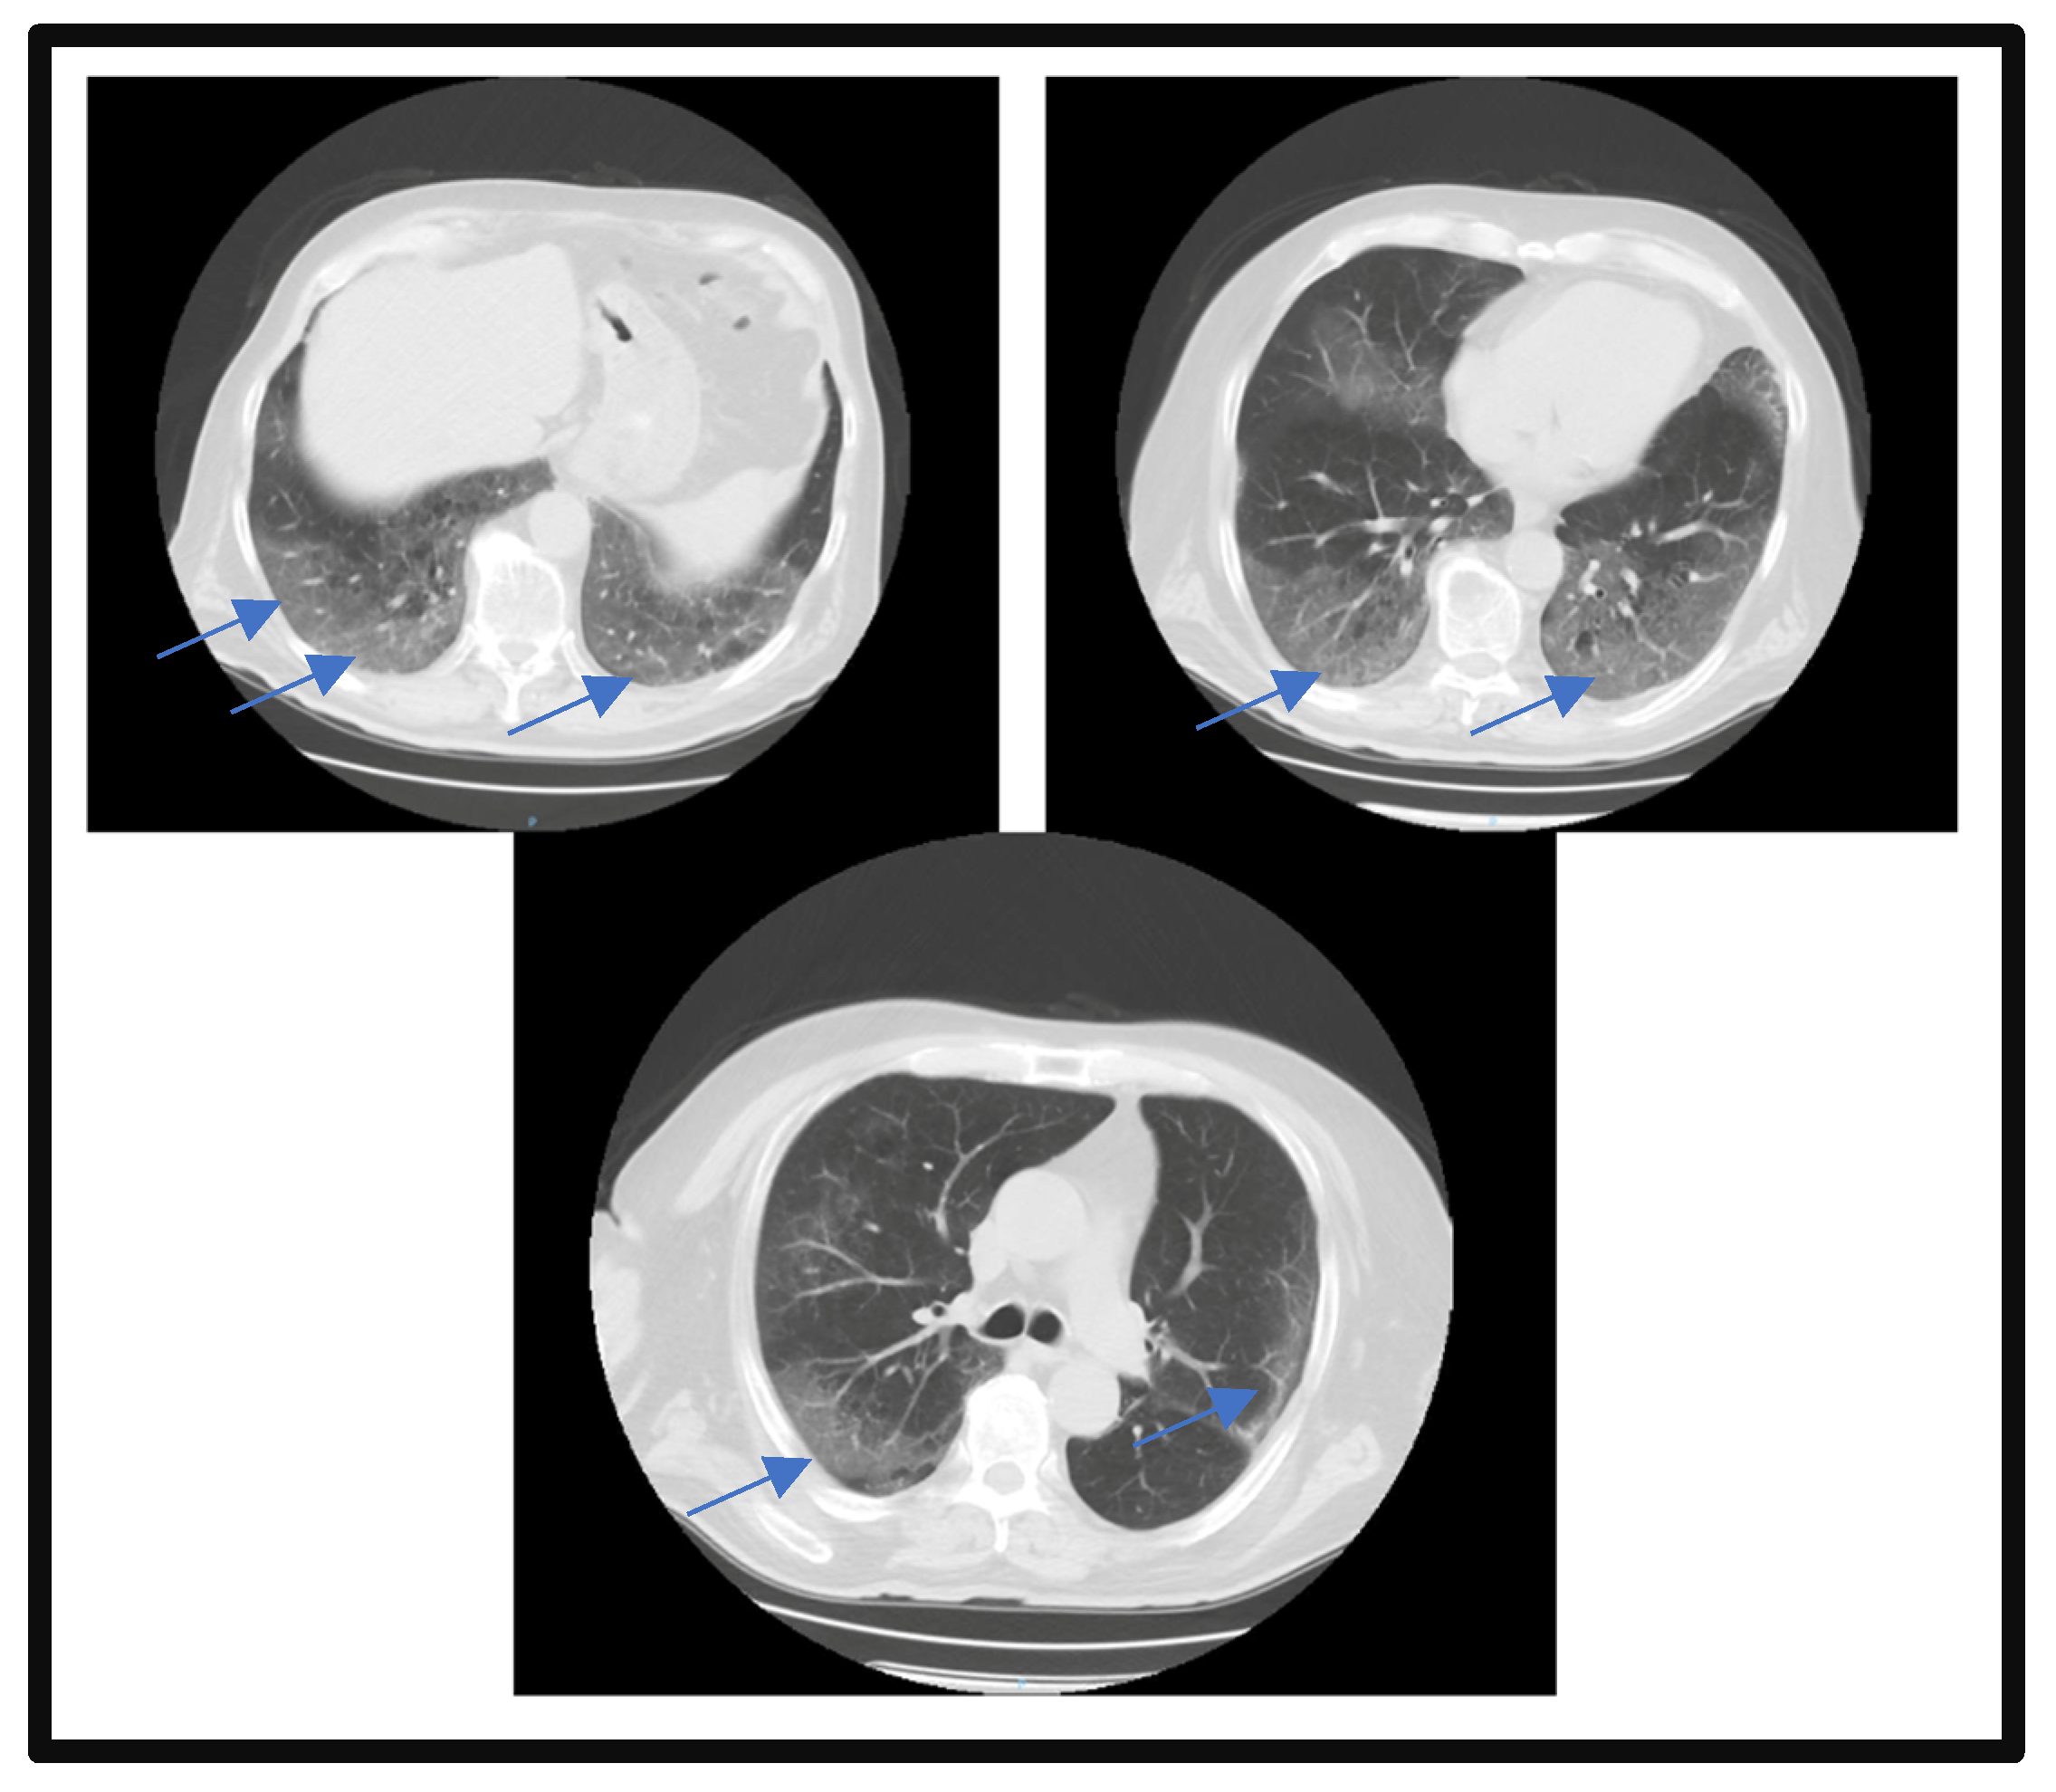

2. Case Report